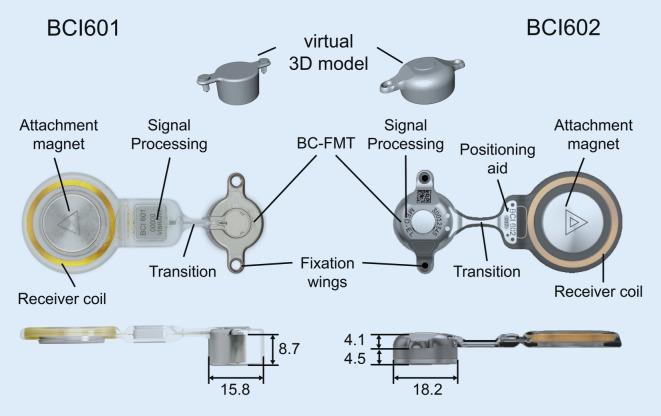

Further development of the BCI 601 (the BCI 602) reduced the penetration depth of the BC-FMT from 8.7 to 4.5 mm. This was achieved by increasing the BC-FMT diameter from 15.8 to 18.2 mm and locating some components of the BC-FMT above the bony surface. With the additional use of 1‑mm spacing washers (BCI 602 Lifts), the implantation depth can be further reduced to 3.5 mm. This configuration elevates the BC-FMT to 5.1 mm above the bony surface. The anchor holes in the fixation wings are 24.4 mm apart (BCI 601: 23.8 mm; Fig. 1).

Fig. 1.

Comparison of the bone conduction implants (BCI) 601 and 602. Images show the new active bone conduction hearing system, BCI 602 (right), and the previous model, BCI 601 (left), (© MED-EL, Innsbruck, Austria, with permission). Virtual three-dimensional (3D) models of the bone conduction-floating mass transducers (BC-FMT) are used for preoperative planning. All measurements are expressed in millimeters

The implantable component of the bone conduction implant BCI 602 consists of an FMT with the electronics and an attachment magnet surrounded by the receiver coil (Fig. 1). The external part, the audio processor, is held in place by the magnet.

With the new active BCI and its optimized geometry, the anatomical indication range has significantly increased compared to the previous model (BCI 601). A study that performed “virtual surgery” in 151 temporal bones of 81 children and young adults (ages 5 months–20 years) demonstrated that, in all patients aged 12 years and older, the BCI 602 could be completely fitted to the bone. In patients aged 3–5 years, the BCI 602 could be fitted to the bone in 75% of cases. In contrast, a complete bone fit was not achieved with the BCI 601 in any of the temporal bones without BCI lifts [33]. However, the BCI 602 has not been approved for this age group of up to 5 years. A lower penetration depth would entail a reduced volume of the BC-FMT. However, adequate acceleration of the skull, which is necessary for stimulating the inner ear, would be difficult to achieve. The resonance frequency is indirectly, exponentially related to the mass of the BC-FMT (~m−1/2). Thus, for an electromagnetic transducer with a given mass and resonance frequency, a lower penetration depth required a larger diameter (BCI 601: 15.8 mm and BCI 602: 18.2 mm; Fig. 1). This corresponds to a 15% increase in the diameter and a 45% reduction in the volume of the implant bed. The latter was reached by partially translocating the BC-FMT above the skull surface (Fig. 1). Due to the translocation of the electronics (demodulator) into the BC-FMT, the overall “footprint” of the implant has decreased. Consequently, depending on the individual configuration of the temporal bone, implantation in children under 5 years old appears to be possible and has been performed (off-label) in individual cases (Fig. 10).